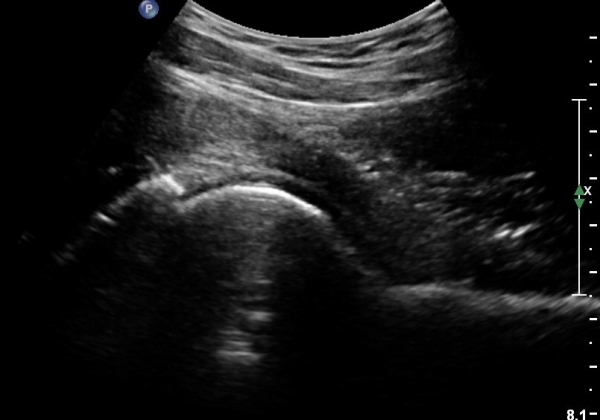

[¾ûµ¢ÀÌ] °í°üÀý Ãæµ¹ÁõÈıº¿¡ÀÇÇÑ È°¾×¸·¿° ÁÖ»çÄ¡·á